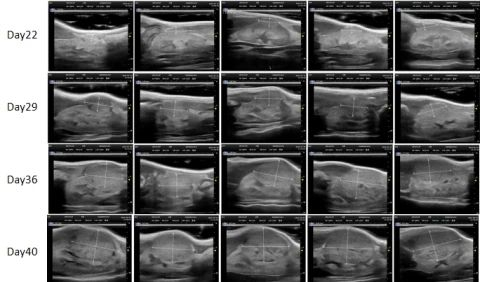

PDX Model (Growth Curve)

部分beats365PDX原位模型展示